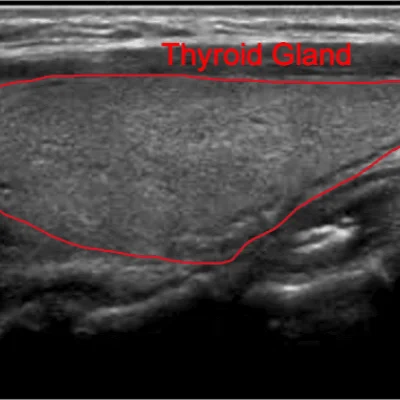

Thyroid

Detect nodules, goiters, or inflammation